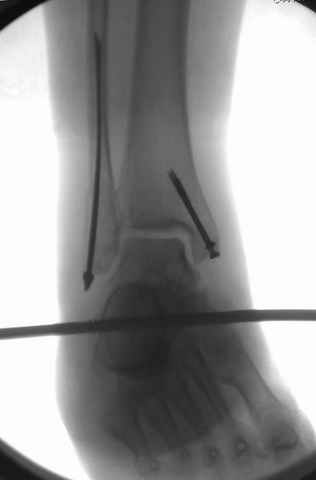

За последнее 10-12 лет после стабилизации малоберцовой кости, стали применять более усовершенный, сложный, хорошо вам известный метод

Илизарова (кстати наряду с тибиал плато, пилон является одним из показанием по применению аппарата Илизарова при травмах) или Hybrid

Fixator, из минимальных доступов комбинированный метод для восстановления суставной поверхности-фиксация каннулированными

шурупами, создания жесткой системы фиксации до сращения перелома, защита от вальгусной деформации и на место образовавщегося метафизарного дефекта- костная пластика ауто костью или его

синтетические заменители, это сегодняшная тактика лечения.